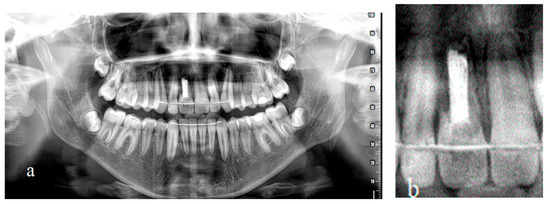

Treatment of an Avulsed and Ankylosed Incisor through Single Tooth Alveolar Osteotomy and Conventional Orthodontic Mechanisms

2. Materials and Methods

3. Results